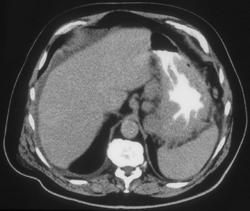

Gastric Lymphoma